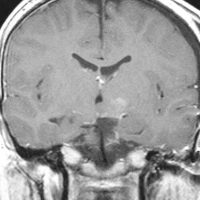

少年期にgelastic seizureで発症

少年期に難治性の発作を生じて悪化しました,これを有茎 pedunculated とするかどうか微妙なところです

術後のMRIです,pterional approach でしか摘出できない腫瘍でした

高い位置がとどかず少し取り残しました

gelastic seizureは減荷されましたが残り,術後に視野欠損を後遺しました